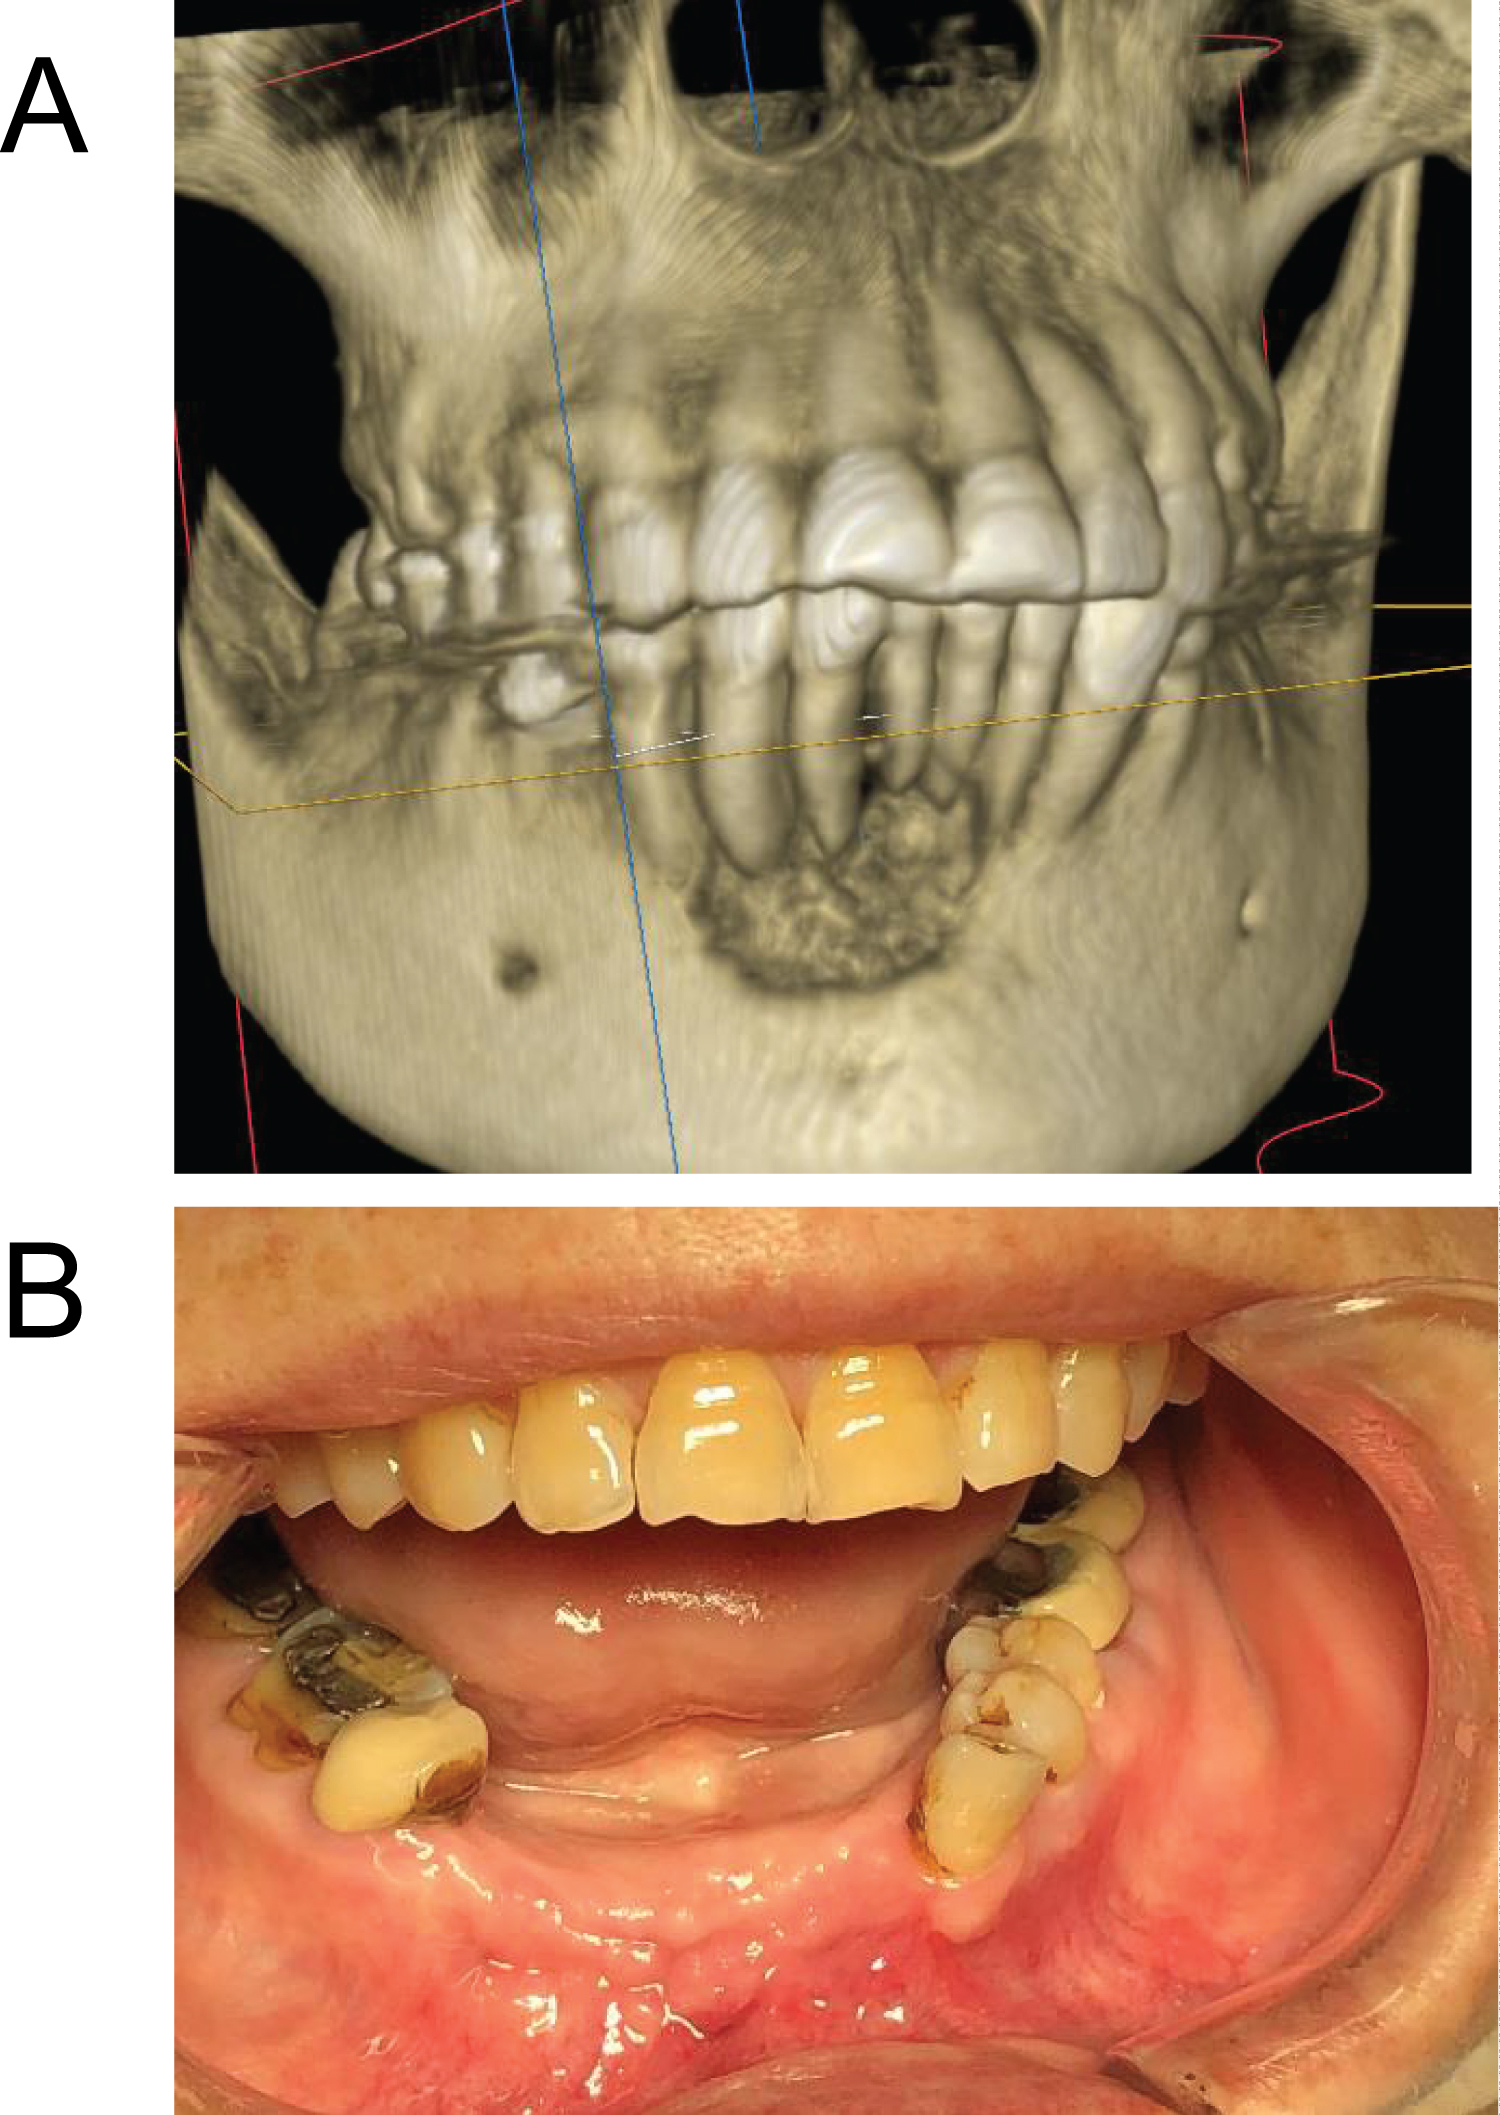

An 82-year-old female had osteoporosis which was treated with zoledronate in the form of Reclast for two years (one 5 mg infusion per year) following which she developed pain and swelling in the anterior mandible. Her lower anterior teeth were mobile with a yellowish purulent discharge from the lesion (Figure 2a). Six mobile anterior teeth were removed, and the lesion was surgically debrided all of the way to sound bleeding bone. Specimens were sent for oral pathology and sulfur granules typical for actinomycosis was found in the pathology specimens. The patient was first treated with oral amoxicillin for three weeks, but the infection was not under control. Surgical debridement was repeated again in the private practice office and the patient received ertapenem infusion through a PICC line for eight weeks. The patient is now fully healed and has been infection free for two years (Figure 2b).

Figure 2: (a) Defect in anterior mandible, illustrated on 3D Cone Beam CT scan; (b) Anterior mandibular wound eight-months postop showing infection free. View Figure 2